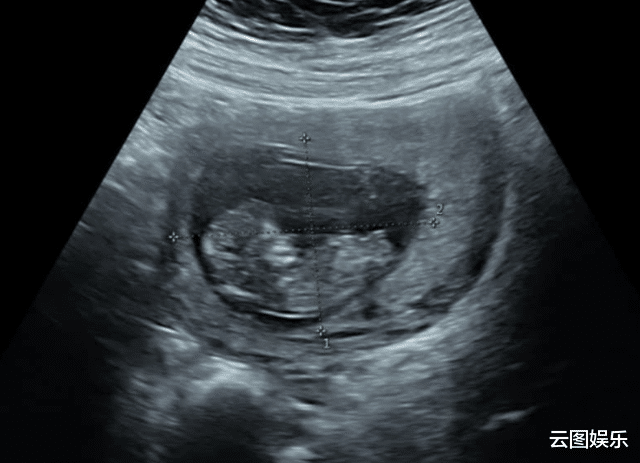

皇天不负有心人 , 她现在终于怀上了宝宝 , 而且已经五个月了 , 进入了稳定期 。 兴奋不已的她 , 表示很感谢幸运之神看到自己 。